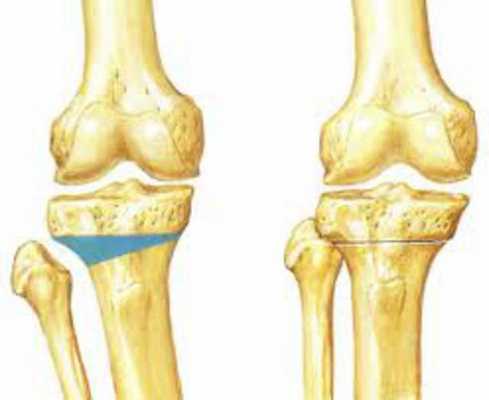

Остеотомия – это хирургическая манипуляция, суть которой заключается в создании «искусственного перелома». Во время операции кость распиливают на две части. После этого костные фрагменты смещают в нужном направлении и фиксируют в анатомически выгодном положении.

В клинической практике остеотомии чаще всего используют для коррекции осевых и торсионных деформаций нижних конечностей. Такие операции делают при дисплазии тазобедренных суставов, несоответствии длины ног, плоскостопии, вальгусной деформации стопы, искривлениях верхних конечностей и позвоночника. Во время хирургических вмешательств хирурги могут распиливать длинные трубчатые кости, позвонки, кости таза или стопы.

Основная цель остеотомии – коррекция распределения нагрузки на суставы. С помощью хирургического вмешательства врачи могут восстановить нормальное функциональное состояние суставов или «разгрузить» их поврежденные части.